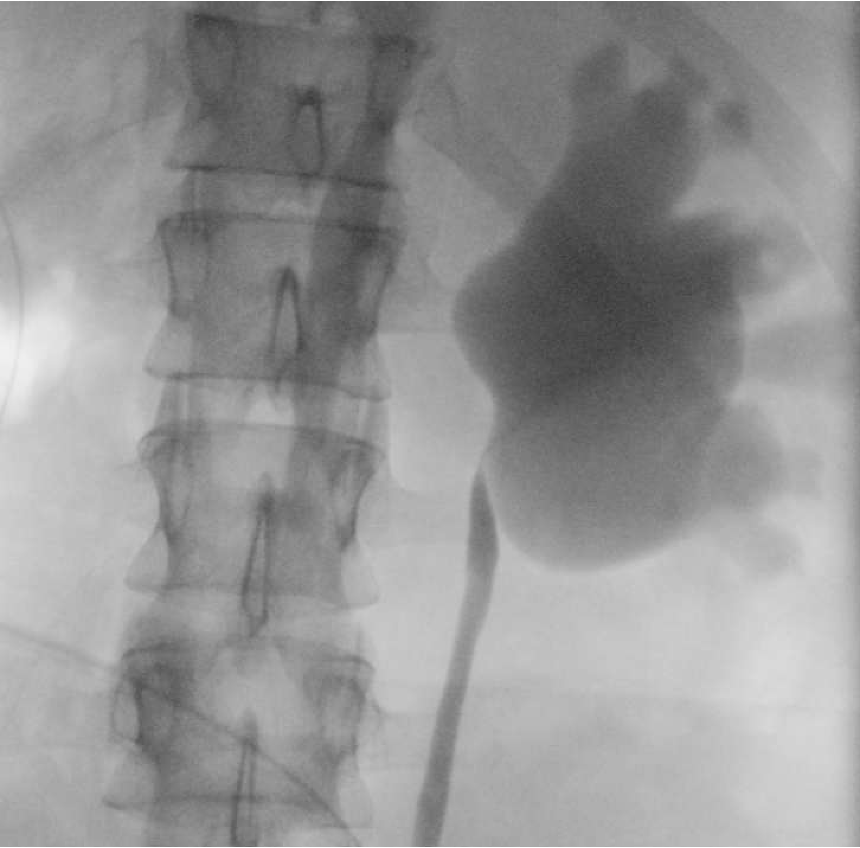

At the conclusion of the procedure, the patient was repositioned and a retrograde pyelogram performed on the contralateral side. This demonstrated a left UPJ obstruction (Figure 2).

After discussion with his family, we opted to return for reconstruction of the left collecting system at a later date. A ureteral stent was placed to decompress the system and protect his functionally (and now anatomically) solitary kidney in the interim. He recovered without incident and creatinine subsequently nadired at 0.87 mg/dL (eGFR; 118 mL/min/1.73 m2).